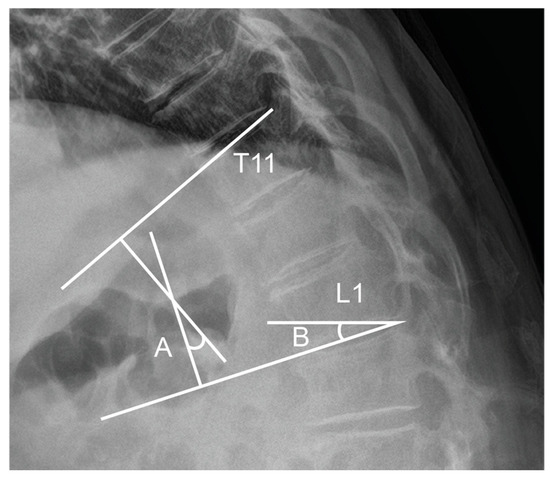

- Preoperative planning: The TLA and TLS were measured on standing lateral radiographs to define each patient’s baseline physiological curvature at the thoracolumbar junction. These values served as intraoperative references for targeted alignment.

- Controlled distraction: Distraction was sequentially applied between UIV–UIV-1 and UIV-1–UIV-2 using a rod distractor or compressor system. Under radiographic guidance, distraction was adjusted with the goal of producing a segmental kyphosis 5° to 10° greater than the angle measured between UIV and UIV-2 in the prone position. Set screws were progressively tightened during this process to maintain the desired curvature and ensure gradual stress distribution.

- Moon, H.J.; Bridwell, K.H.; Theologis, A.A.; Kelly, M.P.; Lertudomphonwanit, T.; Lenke, L.G.; Gupta, M.C. Thoracolumbar junction orientation: A novel guide for sagittal correction and proximal junctional kyphosis prediction in adult spinal deformity patients. Neurosurgery 2021, 88, 55–62. [Google Scholar] [CrossRef]

- Ham, D.-W.; Kim, H.-J.; Park, S.-M.; Park, S.J.; Park, J.; Yeom, J.S. The importance of thoracolumbar junctional orientation, change in thoracolumbar angle, and overcorrection of lumbar lordosis in development of proximal junctional kyphosis in adult spinal deformity surgery. J. Neurosurg. Spine 2022, 37, 874–882. [Google Scholar] [CrossRef]